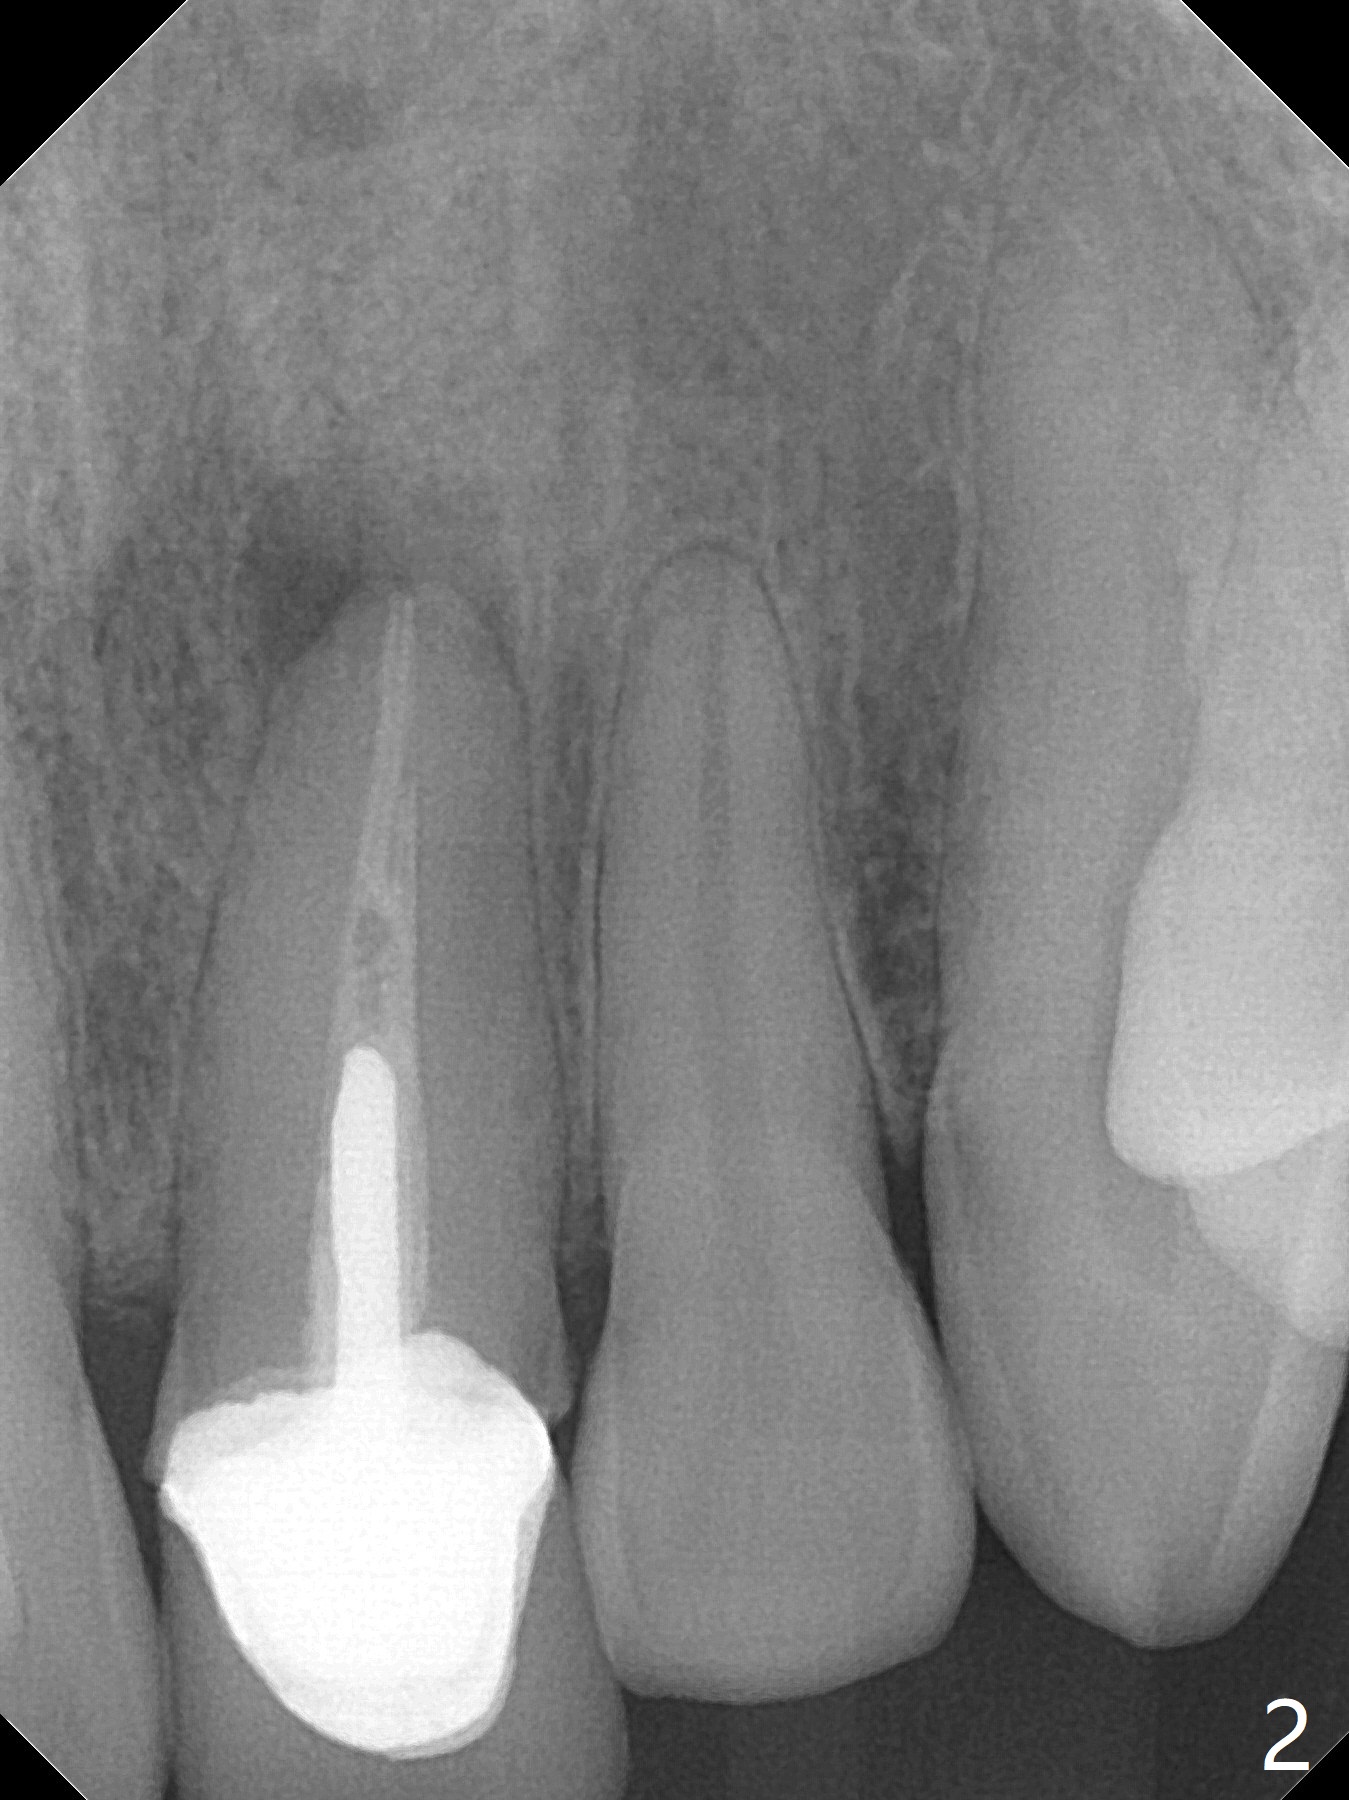

42岁男,小的时候做过矫正,据说智齿萌出后,畸形复发(图一至三)。临床检查显示:上前牙前突,下门牙拥挤,磨牙二类咬合。头颅侧位定位片证明Class II Division I Malocclusion (图四至六):SNA 84.63, SNB 76.11, ANB 8.52。 下周病人复诊,将拍摄照片,取模。正在考虑是否需要拍摄CT,排除上,下切牙是否位于牙槽骨唇侧,有利于做出拔牙决定。